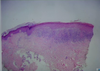

Pathology?

Hyperkeratosis

Parakeratosis

acanthosis might be hard to see from this magnification

neutrophils in the stratum corneum